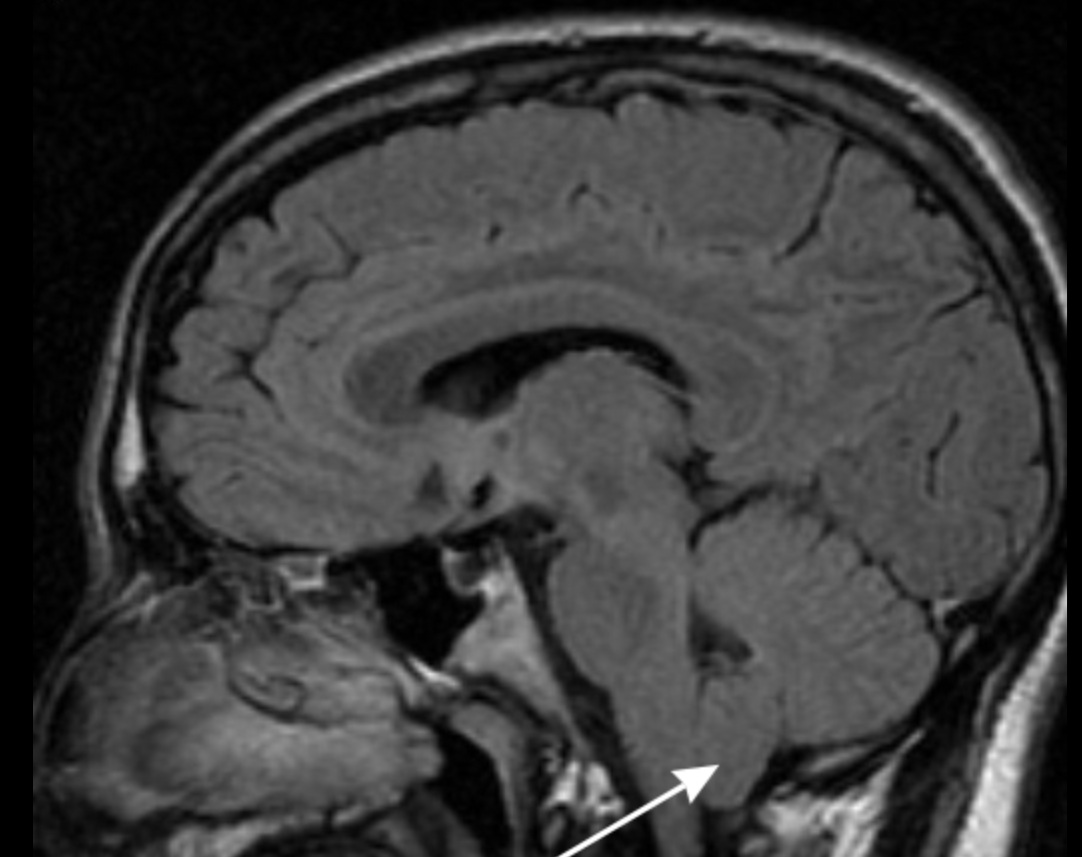

Estenosis lumbar o cervical, claudicación neurógena y planificación de descompresión dirigida.

Correlación clínico-radiológica y decisión de descompresión según síntomas y hallazgos.